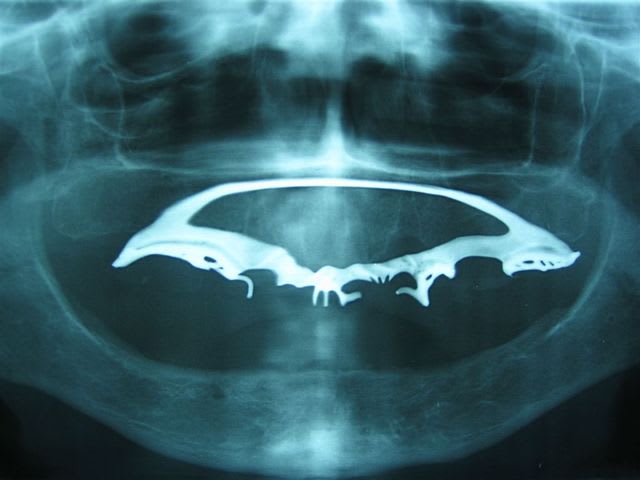

Tu as déjà vu une PPA dont le crochet (la dent correspondante est absente depuis longtemps) est incarné et tient dans son logement qu'il s'est crée dans la lèvre inférieure?

Ta deuxième photo fait penser aux implants transfixiants de Samy Sandhaus... La preuve que ça marche...